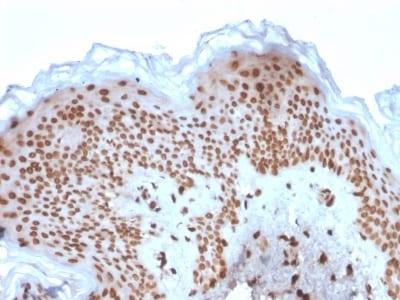

Positive Control

K-562, HeLa or Jurkat cells. Kidney or Skin

Nuclear membrane

IF (verified)|IHC, FFPE (verified)|WB (verified)

Higher concentration may be required for direct detection using primary antibody conjugates than for indirect detection with secondary antibody|Immunohistology (formalin): 1-2 ug/mL for 30 minutes at RT|Staining of formalin-fixed tissues requires boiling tissue sections in 10 mM citrate buffer, pH 6.0, for 10-20 minutes followed by cooling at RT for 20 minutes|Optimal dilution for a specific application should be determined by user